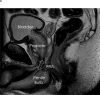

Conclusions: A greater preoperative MUL is significantly and positively associated with a return to continence in men following RP. Magnetic resonance imaging measurement of MUL is recommended prior to RP.

Patient summary: We examined the effect that the length of a section of the urethra (called the membranous urethra) had on the recovery of continence after radical prostatectomy surgery. Our results indicate that measuring the length of the membranous urethra via magnetic resonance imaging before surgery may be useful to predict a longer period of urinary incontinence after surgery, or to explain a delay in achieving continence after surgery.